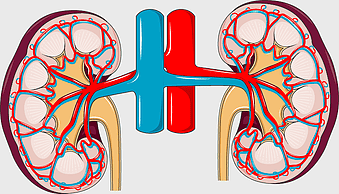

Pulmonary edema symptoms, chronic obstructive pulmonary disease diagram, kidney failure effects on lungs, pulmonary circulation illustration, lung disease diagnostic, respiratory health visuals, human anatomy respiratory system, PNG

- pulmonary edema symptoms

- chronic obstructive pulmonary disease diagram

- kidney failure effects on lungs

- pulmonary circulation illustration

- lung disease diagnostic

- respiratory health visuals

- human anatomy respiratory system

chronic kidney disease illustration, tubulo renale health, kidney function diagram, renal health awareness, kidney disease symptoms, urinary system health, kidney care tips -

kidney anatomy, human kidney illustration, kidney cancer awareness, kidney organ diagram, renal system structure, medical kidney image, urinary system components -

kidney failure, acute kidney failure, chronic kidney disease, dialysis treatment, renal health, medical icon, kidney function -

chronic kidney disease illustration, nephron structure diagram, kidney transplant medical image, excretory system anatomy, renal blood flow visualization, human kidney cross-section, medical education graphics -

kidney anatomy diagram, human kidney structure, retroperitoneal space illustration, blood vessels in kidneys, renal system visualization, medical kidney illustration, kidney cross-section analysis -

kidney anatomy diagram, human kidney structure, adrenal gland and kidney, kidney stone illustration, renal system diagram, urinary system anatomy, kidney blood vessels -